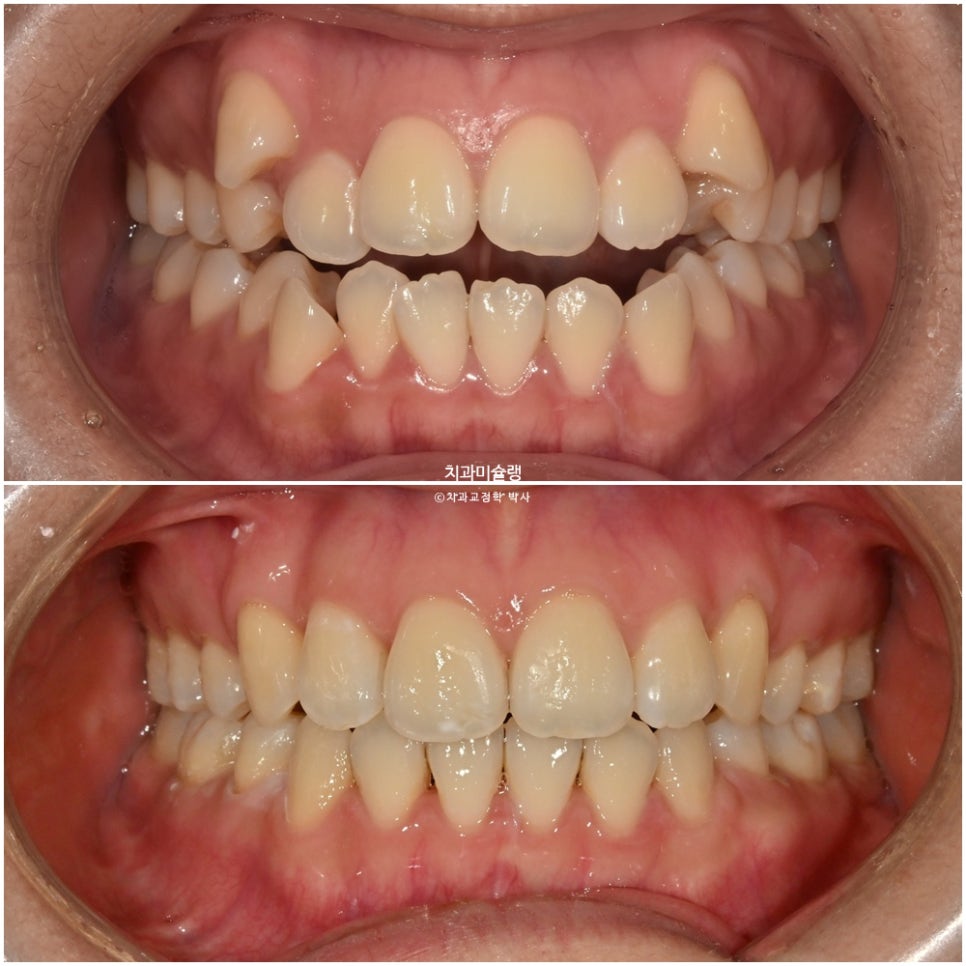

초진 시 환자 상태

2023년 9월 내원

덧니와 개방교합 때문에 오신 환자분 입니다.

덧니가 상당히 심한편입니다.

앞니뿐 아니라 작은어금니까지 또있는 개방교합입니다.

어금니 교합관계는 2급 입니다.

덧니를 제자리 시키려면 발치가 필수적인 상황입니다만

입매를 보면 하관에서 인중이 차지하는 비율이 크고 입술이 얇습니다.

치료 결과 비교

이제 전후비교 보겠습니다.

중심선은 잘 맞으며 송곳니는 제자리로 잘 내려왔죠. 개방교합도 완벽히 개선되었습니다.

어금니 교합은 이미 좋습니다.

중심선 교합은 좋고 발치공간도 타이트 하게 마무리 되었습니다.